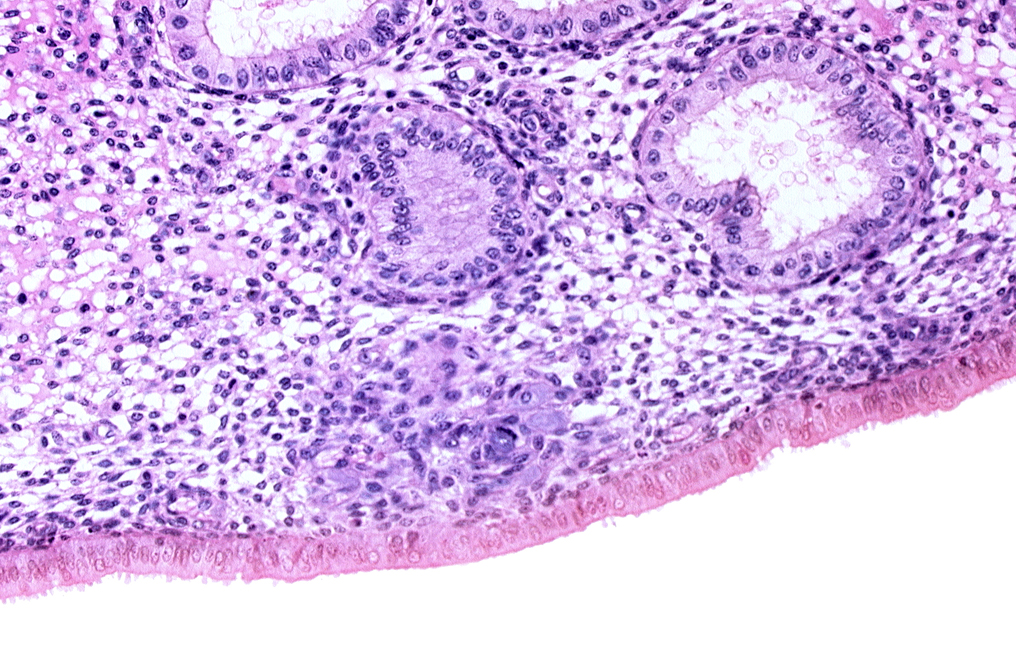

Carnegie Embryo #8020 | Location: 05-04-04

Keywords: edematous endometrial stroma (decidua), endometrial epithelium, endometrial gland, endometrial sinusoid, lumen of endometrial gland, solid syncytiotrophoblast

Source: The Virtual Human Embryo.